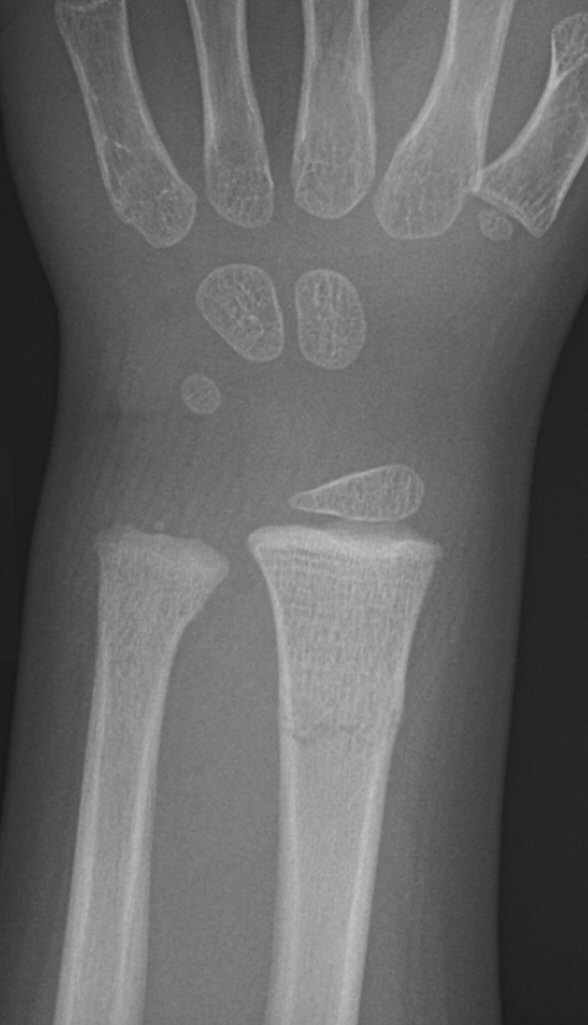

Dorsalbockad distal radiusfyseolys Salter-Harris typ 2 före och efter reposition